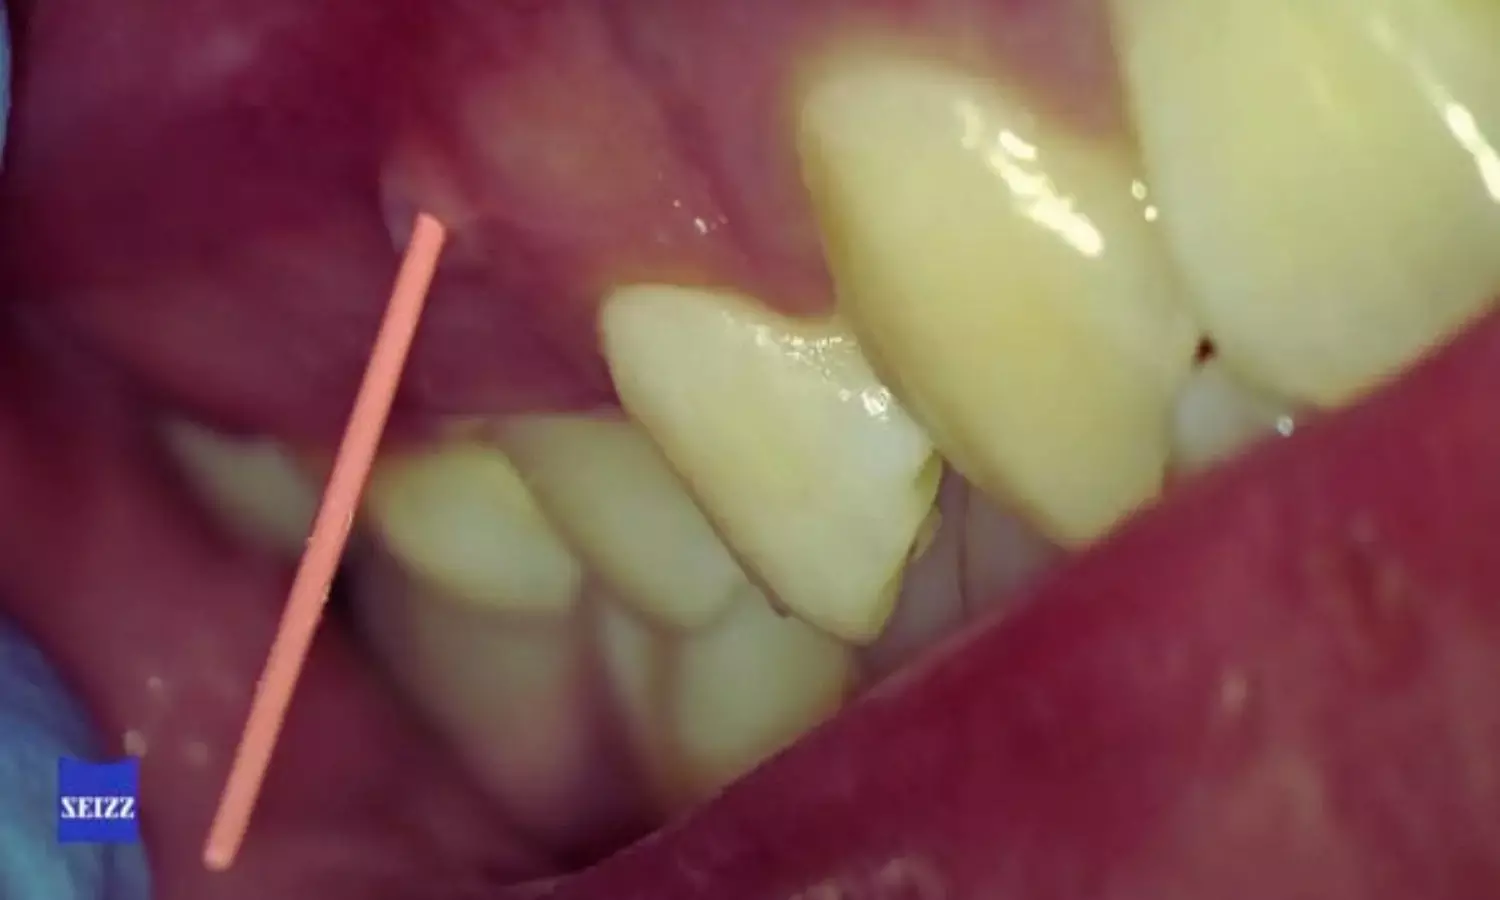

Accurate diagnosis is critical in cases where pulp and periodontal tissues are both involved, as clinical and radiographic features often overlap. Traditional periapical radiography remains a first-line imaging modality in dental practice due to its accessibility and low radiation dose. However, its two-dimensional nature can limit visualization of intricate anatomical details, potentially leading to misinterpretation of complex lesions. CBCT, by contrast, provides three-dimensional imaging that can reveal structures and pathologies not clearly visible on standard radiographs.

In the cross-sectional study, the investigators recruited 60 dental specialists—30 endodontists and 30 periodontists—who evaluated ten carefully selected clinical cases. These cases represented a range of challenging conditions, including vertical root fractures or fissures, endodontic perforations, persistent apical periodontitis, combined endo-periodontal lesions, and localized periodontitis. Each participant assessed the cases at two separate stages.

• The PR+CBCT combination was especially effective in identifying endo-periodontal lesions, including cases with and without associated root damage, compared with periapical radiography alone.